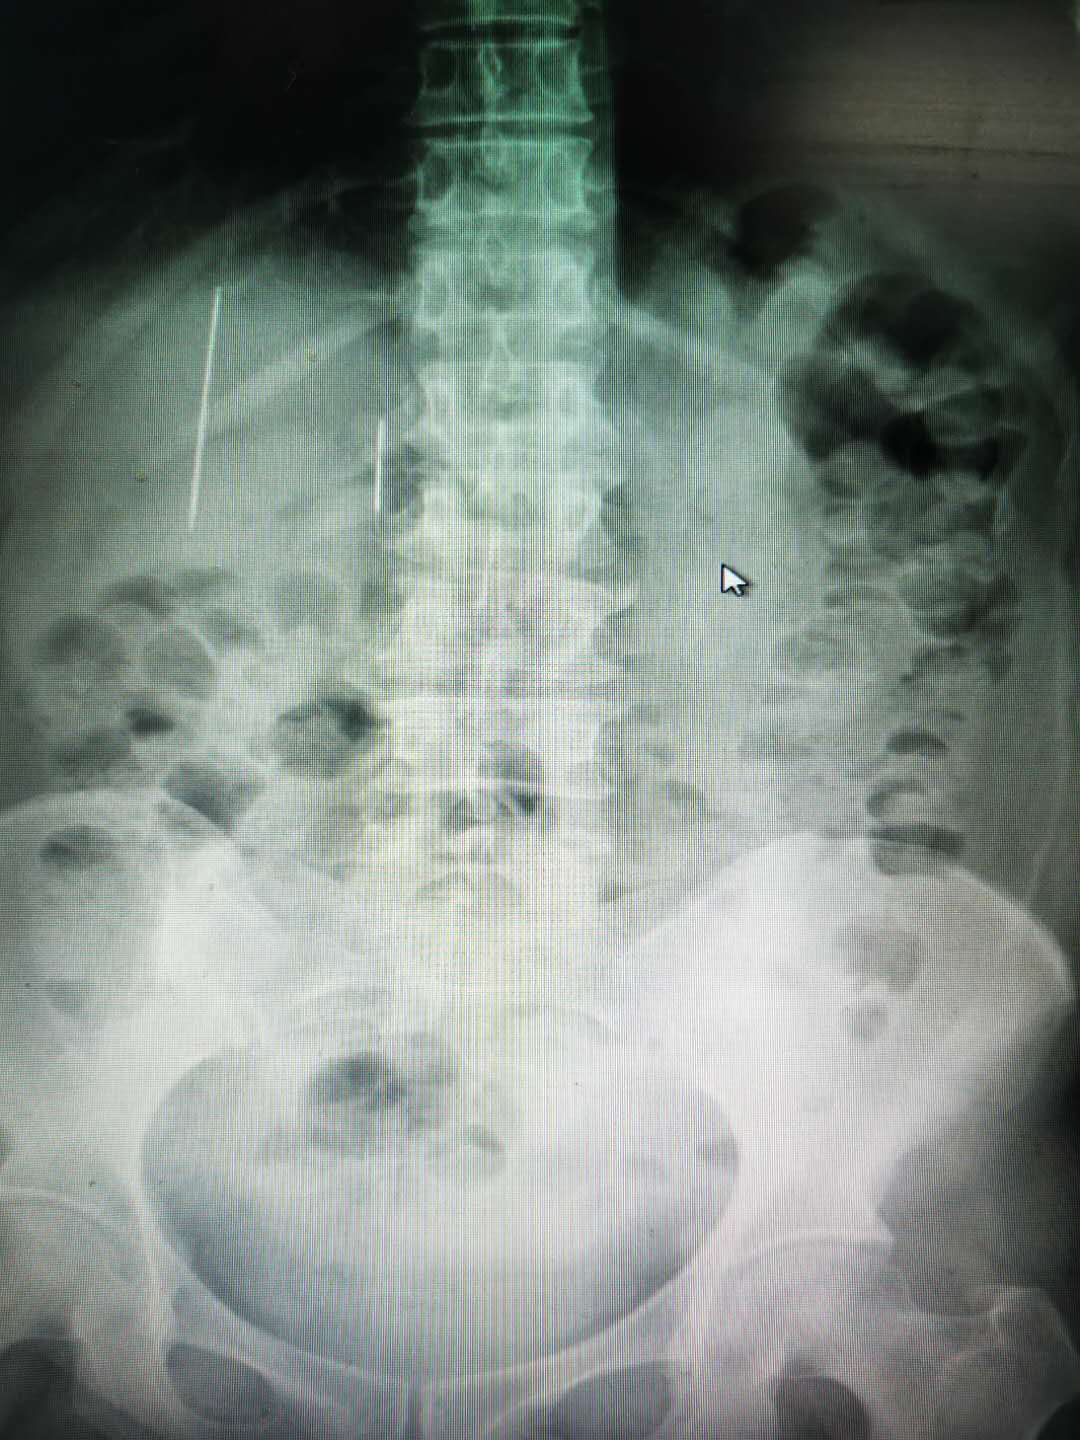

經入院後影像CT顯示,王女士的肝區有兩根針狀金屬密度影,尖端外露,有進一步損傷大血管及肝臟的危險,時刻危及生命。普外二科吳非主任緊急安排手術方案,經過何立偉主任醫師主刀,在與王迪主治醫師及麻醉專家密切配合下,經過約2小時,成功為王女士施行了肝破裂修補加十二指腸破裂修補術,順利將王女士腹部的兩根金屬針取出,兩根針因在肚子裏時間過久已變成黑色,一根長約9cm,另一根長約6cm,術中醫生們仔細修補好王女士的肝臟破裂口及十二指腸破裂口,徹底止血,術後複查腹部平片未見明顯異常,王女士現在已無生命危險,處於術後的康復階段。